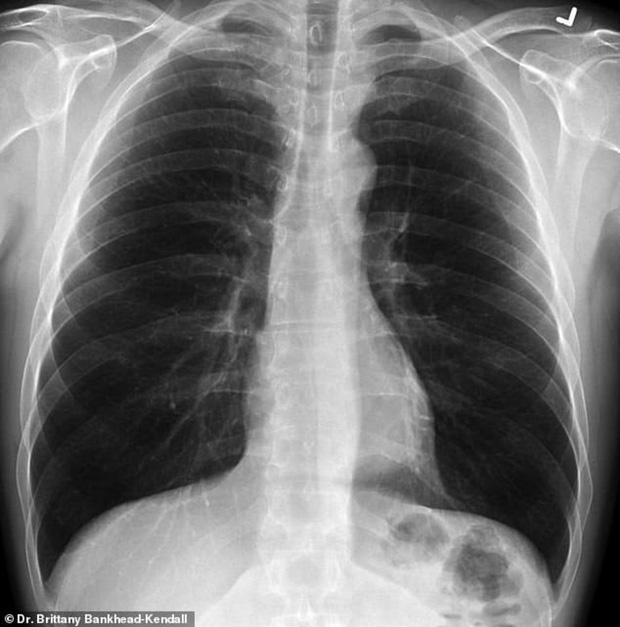

Bác sĩ phẫu thuật Brittany Bankhead-Kendall ở Trung tâm Khoa học Sức khỏe Đại học Kỹ thuật Texas (Mỹ) mới đây trưng ra 3 tấm phim chụp X-quang: Một của bệnh nhân khỏe mạnh, một của người hút thuốc, và một của bệnh nhân Covid-19.

Phim của người khỏe mạnh có nhiều khoảng đen, cho thấy họ có thể hít vào đủ lượng oxy cần thiết. Phim chụp phổi người hút thuốc thì có nhiều khoảng mờ, còn của bệnh nhân Covid-19 thì gần như trắng xóa.

Phổi khỏe mạnh. Ảnh: Bác sĩ Kendall.

Những khoảng mờ trên phim chụp phổi thường là chỉ dấu của dịch lỏng, vi khuẩn, hoặc tổn thương và vết sẹo.